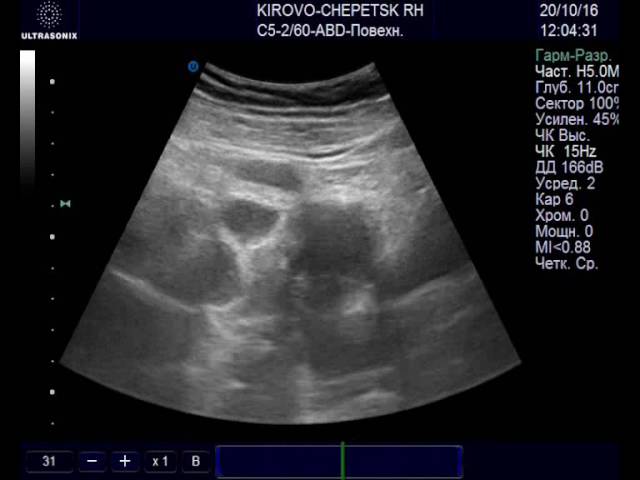

Описание лютеиновой железы на УЗИ:

| Параметры | Эхопризнаки | Как выглядит |

| Внешний вид | Гетерогенное анэхогенное образование | На яичнике округлое темно-серое пятно с черными вкраплениями и единичными белыми точками |

| Структура | Гиперэхогенное образование с крупными зонами низкой плотности (гипо- или анэхогенными очагами) | Серое пятно с большой площадью затемнений. Окрашены черным места скопления крови, локализации сосудов |

| Размер | В норме до 30 мм, при образовании кисты – более 3 см | Диаметр ЖТ сверяют с нормой по фазам желтого тела |

Если диагност выявил два желтых тела или больше, в протоколе УЗИ описывается каждое образование. Растущая и угасающая железа неодинаково выглядит. С началом регрессии она уменьшается, светлеет. Черное пятно без вкраплений – эхопризнак жидкостной кисты.